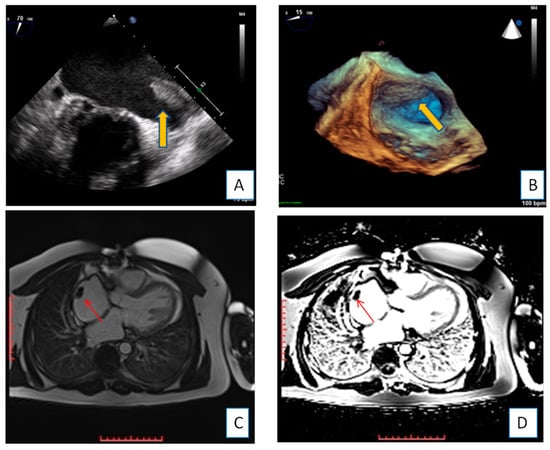

3.1. Transthoracic Echocardiography

3.2. Transesophageal Echocardiography